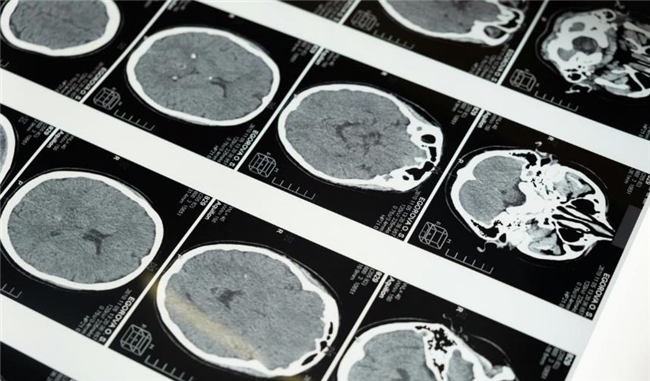

提到脑卒中,很多人会混淆 “出血性”和“缺血性”,简单来说,出血性和缺血性脑卒中的核心区别在于“破”与“堵”。出血性脑卒中属于脑血管破裂导致血液溢出,从而压迫脑组织,常引发剧烈头痛;而缺血性脑卒中则是因血栓导致血管闭塞,血流不通,脑组织因缺血缺氧而受损,通常表现为手脚无力或麻木。两者发病机理截然不同,一个是血管“漏了”,一个是血管“堵了”。但对占大多数的缺血性脑卒中来说,救治的核心逻辑只有一个:尽快溶解堵塞血管的血栓,恢复脑部供血。

很多人对溶栓治疗存在误解,认为溶栓治疗可能会增加颅内出血的风险,但这种风险的发生率极低,且医生会在治疗前进行严格评估,通过头颅 CT 等检查排除出血性脑卒中,同时评估患者的年龄、基础病、凝血功能等指标,权衡利弊后再决定是否进行治疗。相比之下,错过溶栓时间导致的终身残疾,对患者和家庭的影响更为深远。